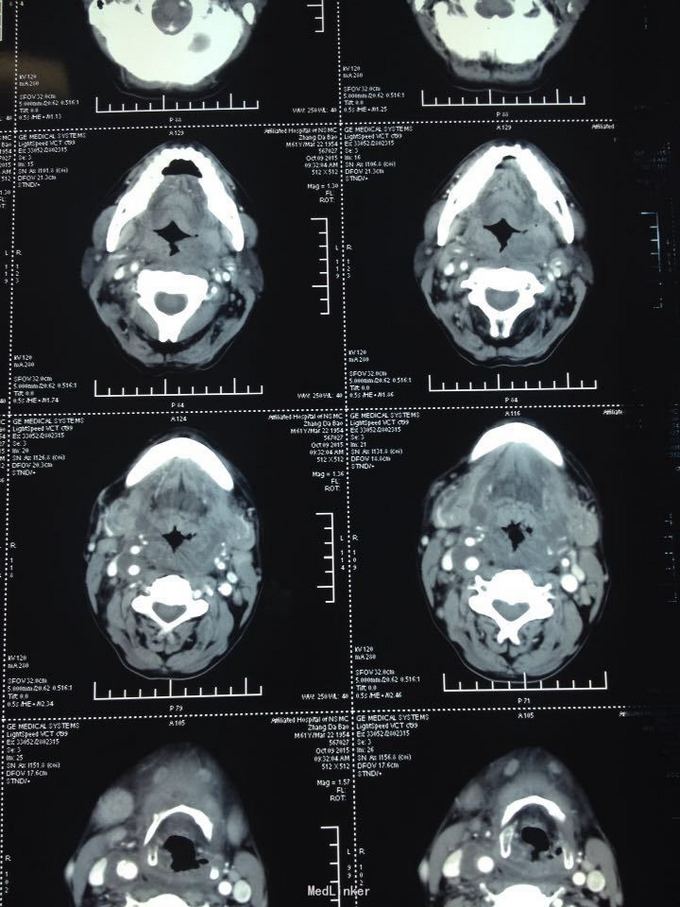

颈部肿痛10多天。10多天前无明显诱因出现颈部及颌下疼痛,肿胀明显,吞咽受限,无伴明显呼吸困难。无高热、寒战等。未特殊处理,上述症状渐加重。

双侧颈部肿胀明显,皮肤稍充血,皮温较高,可触及波动感,压痛明显,右侧为甚,咽部黏膜充血肿胀明显。

颈部多发脓肿。入院后完善相关检查,给予抗感染、对症支持治疗,并于急诊全麻下行颈部脓肿切开引流术,术中分离右侧颈动脉鞘,充分分离脓腔,充分引流。